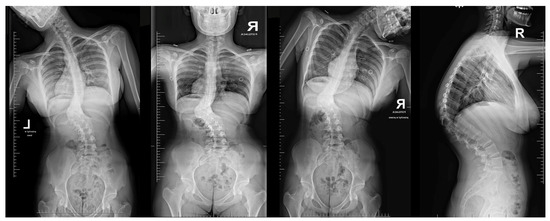

Upon conducting a postoperative physical examination, it was observed that the patient’s shoulder symmetry and rib hump had improved significantly without any neurological or other complications. Figure 9 shows a significant improvement in the patient’s posture, sagittal balance (focal thoracic kyphosis from 108° to 43°), and coronal balance (from 63° to 25°). The patient was discharged 5 days after surgery; no brace was ordered. Figure 10 and Figure 11 show the X-rays and 3D-CT of the patient at the final follow-up.

Figure 10. Standard standing AP (a) and lateral (b) X-rays of the 16-year-old female after undergoing surgical treatment at 2 years of follow-up.